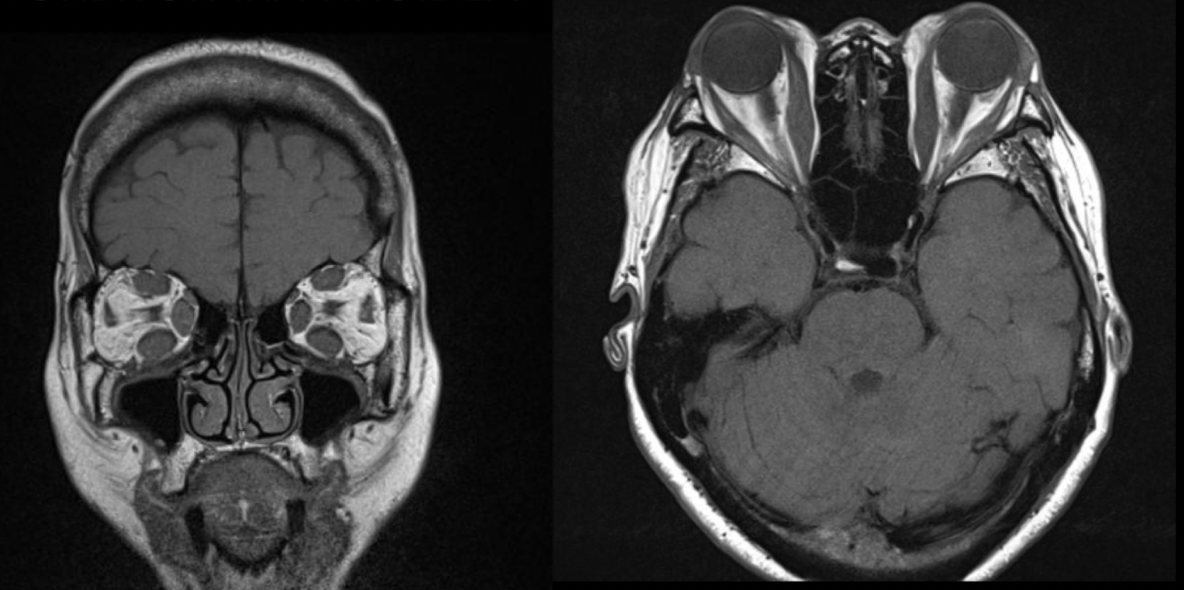

¿qué nos permite ver RM en retinoblastoma?

• Evaluar implicaciones intra y extra oculares

• Identificar hemorragia retinal

¿de qué enfermedad nos hablan las siguientes imagenes?

Retinoblastoma cuadrilateral